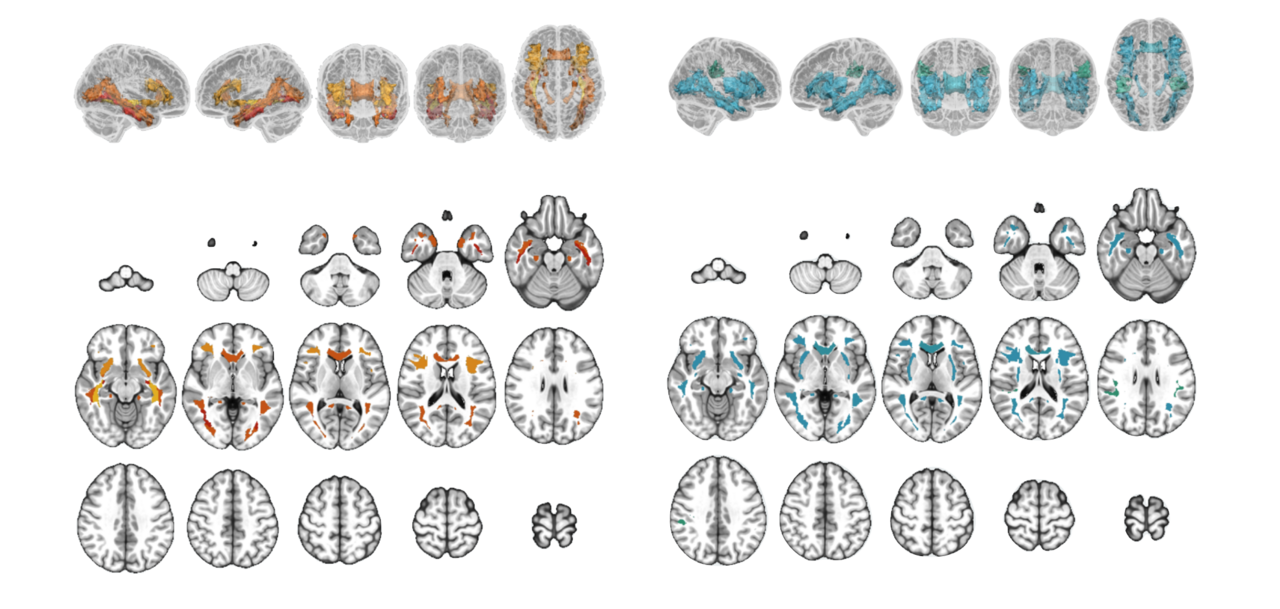

Relationship between tau and white matter microstructure in DLBs. Statistically significant associations of cortical [18F]-Flortaucipir with regional DTI and NODDI parameters are depicted on 3D glass brain renderings and in volumetric MNI152 space (radiological orientation) after correction for multiple comparisons with FDR. Linear regression models were adjusted for age, APOE genotype, and [11C]-PiB, and corrected for multiple comparisons with FDR. FDR q-values are expressed as -log(q) (i.e., 1.3 -\> q = 0.05).